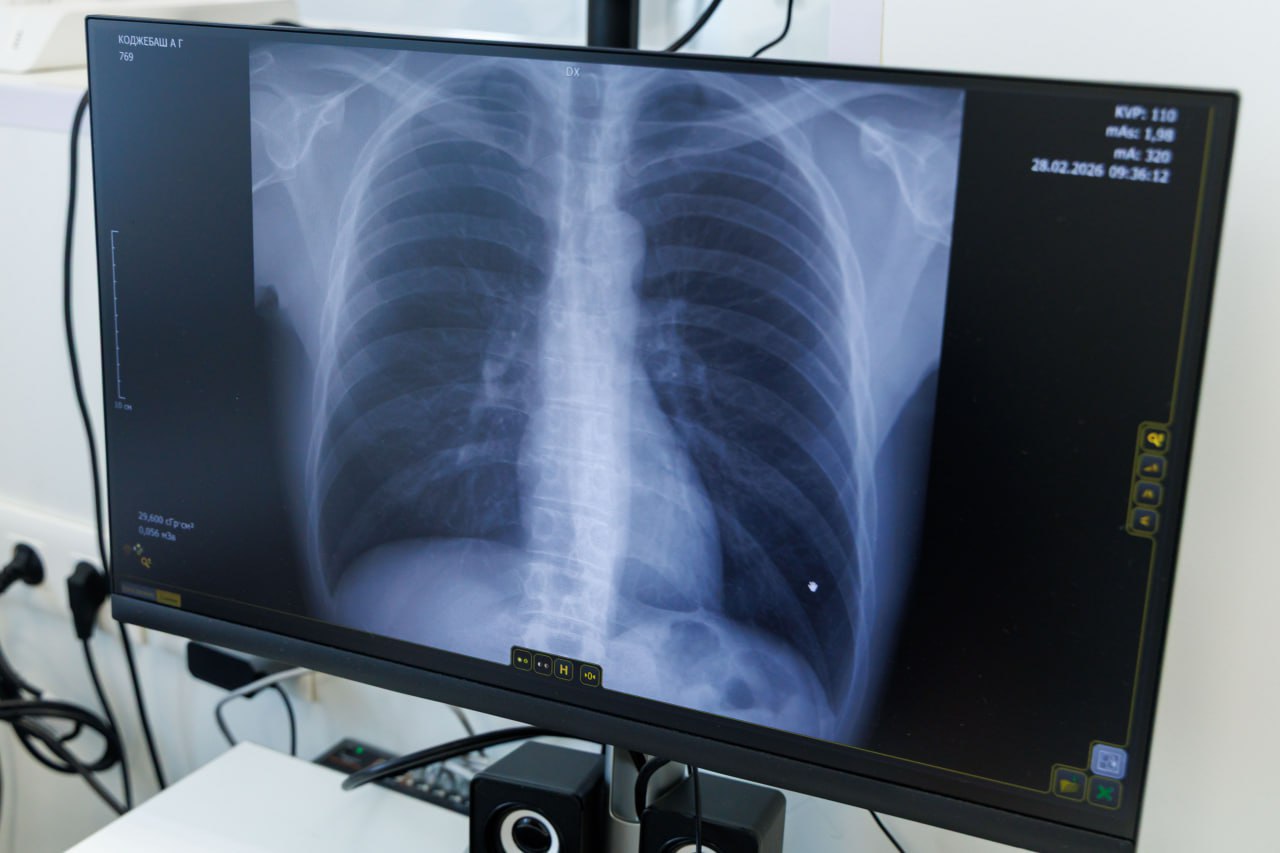

38 человек прошли онкоскрининг в Центре амбулаторной онкологической помощи в Люберецкой больнице в рамках Дня открытых дверей

За день обследование прошли 28 женщин и 10 мужчин. У четверых пациентов были выявлены подозрения на злокачественные новообразования.